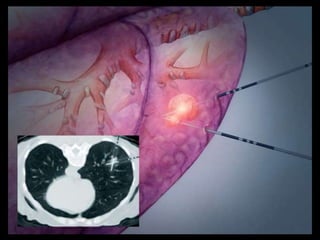

Pulmonary Hamartoma